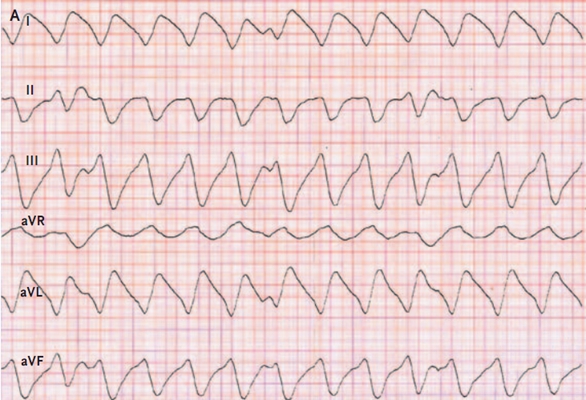

預激綜合症圖片

預激綜合徵心電圖 (82)

預激綜合徵心電圖 (83)

預激綜合徵心電圖 (84)

預激綜合徵心電圖 (85)

預激綜合徵心電圖 (86)

預激綜合徵心電圖 (87)

預激綜合徵心電圖 (88)

預激綜合徵心電圖 (89)

A:預激綜合徵典型的心電圖表現是竇性心搏的PR間期縮短,短於0.12s,而且導聯的QRS波群時間超過0.12s。QRS波群起始部分會有粗鈍,終末部分正常,甚至會導致ST-T波型呈現繼發性的改變,甚至於QRS波群主波方向相反。預激綜合徵是指心房……

A:預激綜合徵是很少見的心律失常,是房室傳導異常的一種類型,提早興奮心室的一部分或全部,引起心室肌提前激動,常合併室上性心動過速。心電圖可見PR間期縮短小於0.12秒;QRS時限延長0.11秒以上;QRS波群起始部粗鈍,繼發性ST-T改變。沒有……

A:預激綜合徵合併房速的時候,心電圖可以出現快速而且寬大畸形的QRS波群,有點類似於室性心動過速,典型的預激波有可能會被覆蓋。合併房速的時候會有極快速的心室率、QRS波群會寬大畸形,也有可能比較易變和複雜。患有預激綜合症合併房速,如果有明顯的心……